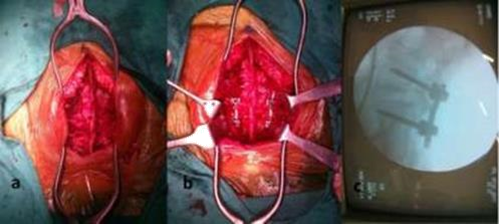

Indication for surgical intervention Symptomatic Spondylolisthesis after adequate conservative treatment. Progressions of a functionally disabling neurologic deficit or caudaequina syndrome, although rarely associated with lumbar Spondylolisthesis, are two indications for urgent operative intervention (Figure 1-4).10

Figure 1 A) Intraoperative photograph showing adequate exposure. B) Shows the four requisite pedicle screws inserted and rods distracted.C) Shows C-arm picture after instrumentation.

Surgical procedure

A total of 18 patients with lumbar Spondylolisthesis were managed surgically by decompression and Posterior lumbar interbody fusion by cage with autogenous bone graft and stabilization by transpedicular screws and rods. The studied was carried out between July 2017 and June 2019. All patients underwent surgical procedure by posterior midline approach. The level of involved vertebra was identified preoperatively by a skin marking under radiological guidance. All the patients underwent surgery under general anesthesia and in prone position on special designed padded operating table for the purpose of abdomen hang free, intravenous pressure was reduced and per operative blood loss was decreased as a result of collapse of the epidural venous plexus. A longitudinal incision was made in posterior midline of lumbosacral region.

To expose the lamina, the facets and transverse process a standard sub periosteal dissection was carried out using self-retaining retractors to maintain tension on soft tissues during exposure and any bleeding was secured by proper haemostasis using bipolar diathermy. Posterior decompression was done by laminectomy and discectomy.End plate was removed by end plate curette. Then pedicle was identified and guide pins were inserted. The position of guide pins were determined by C-arm.

After correcting direction and level, pedicle screws of adequate length and diameter were inserted. The screws placement were rechecked by C-arm. Local bone grafts previously collected from lamina, spinous process, facet were mashed up and packed in an adequate size of titanium cage. Some bone grafts were placed anterior part of the disc space. A curved cage specially designed for the PLIF technique was filled with bone chips and inserted into the posterior or central part of the disc space. The shape of the cage and the 40° angle of the introducer enable a controlled cage positioning.Finally compression was done after placing two rods. The wound was closed in layers with drain kept in situ.